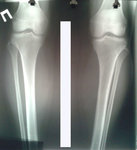

Re: Терачина♥♥♥

Дата операции 03.12.2015г.

Дата снятия аппаратов 09.03.2016г.

Срок лечения 95 дней.

Поздравляю

Результат супер!!!!